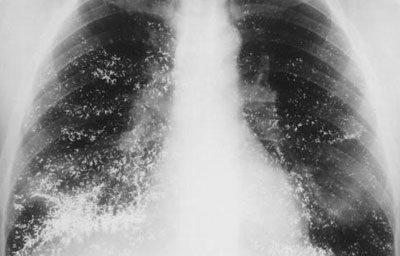

Пневмония развивается за 48 часов пребывания в больнице и поражает альвеолярные ацинусы. У больных, перенёсших операцию, заболевание может развиться быстрее. При рентгене грудной клетки обнаруживаются очаги инфекции.

Нозокомиальная пневмония диагностируется разными методами. Основным обследованием является рентгенография. Её проводят на разных этапах заболевания для диагностики и проверки эффективности лечения. Также после выздоровления больного направляют на рентген, чтобы убедиться, что в лёгких не осталось воспалительного процесса.

Но основываться только на рентгеновских показателях нельзя. Современная медицина располагает различной аппаратурой, предназначенной для диагностики лёгочных заболеваний.

- Рентген показывает наличие одного или несколько очагов воспалительного процесса.